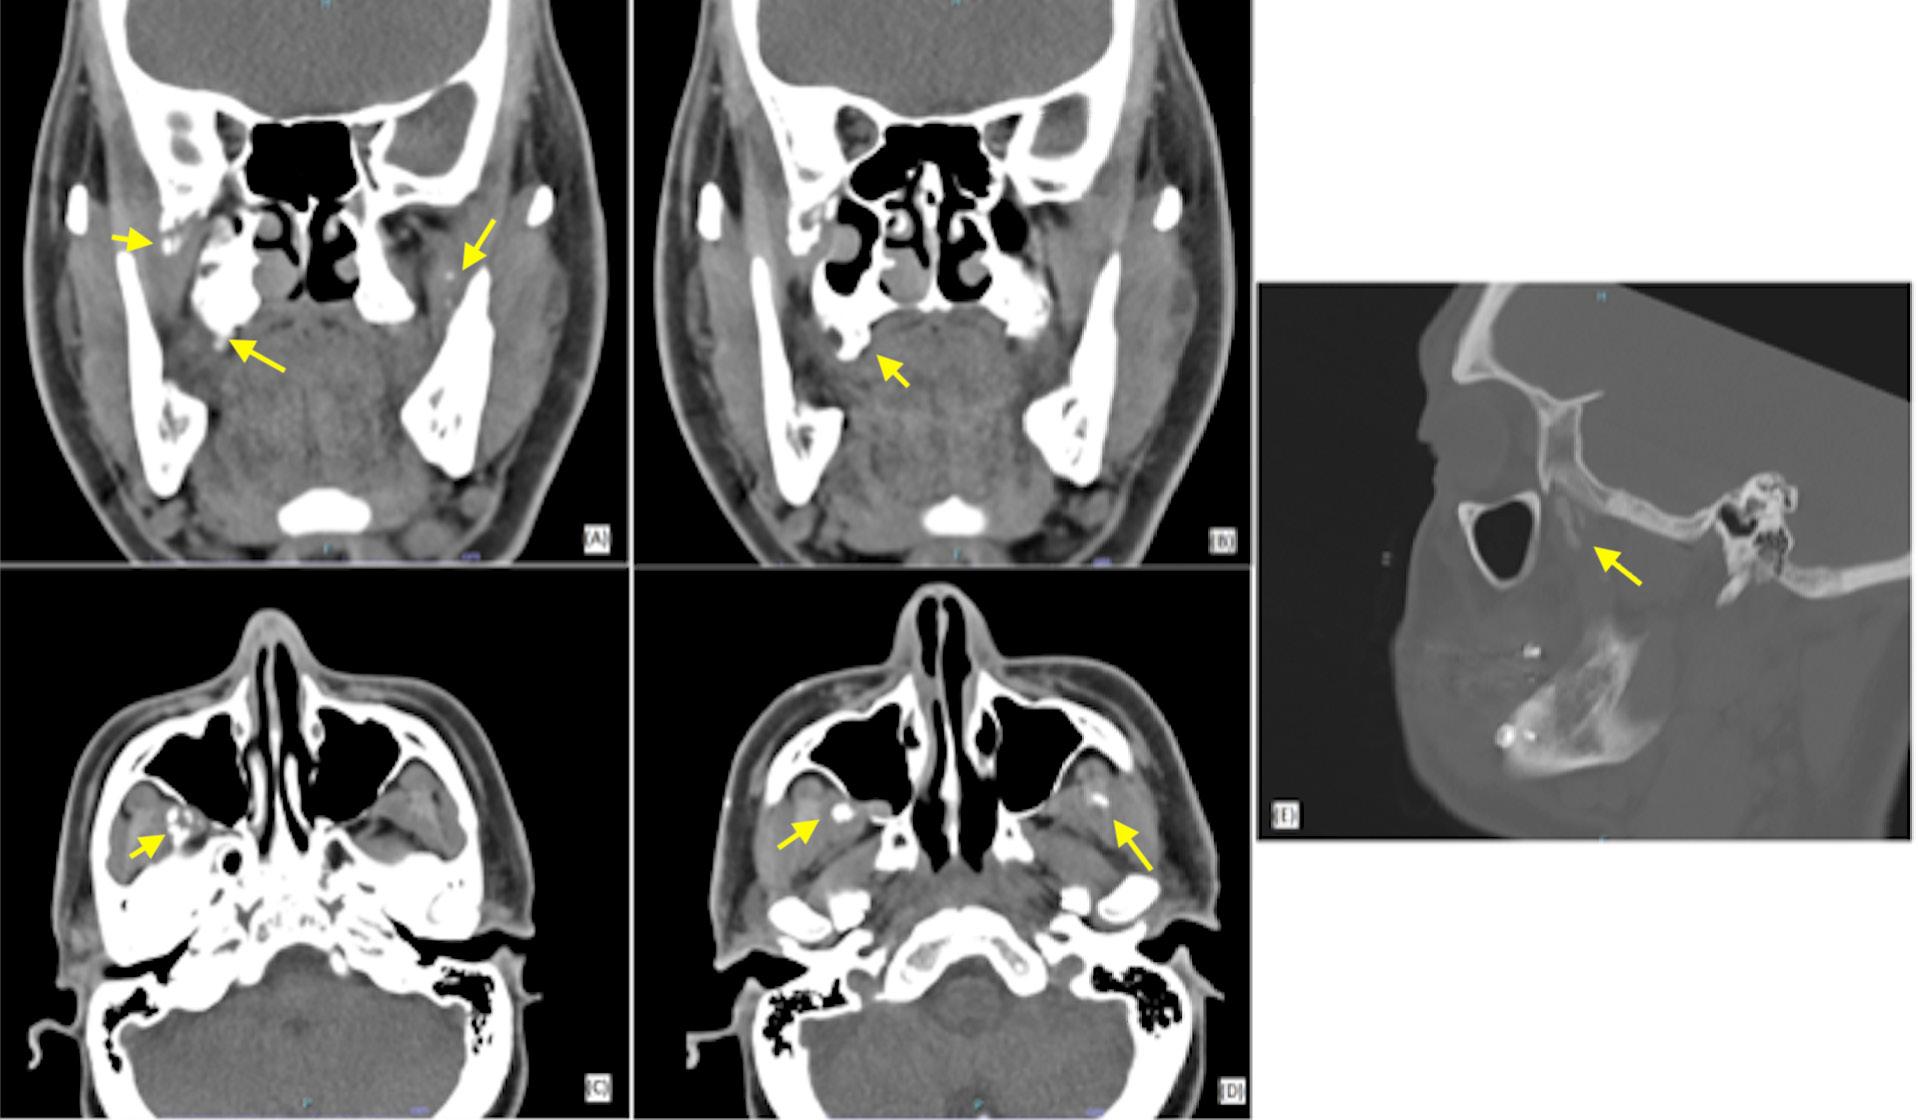

Treatment planning protocol was the same for all individuals and included examination, impressions for study models and a clinical bite record using wax and captured in centric relation (CR, the condyle was in the most superior and posterior position in the glenoid fossa). The clinical bite records and study models were subsequently digitised. A pre-operative medical-grade helical CT image was captured with the individual in a supine position with their lips closed, ensuring gentle occlusion in centric occlusion (CO, the position of maximum intercuspation of the dentition) without a bite registration splint. The CT protocol was derived from KLS Martin Group (KLS Martin Group, Germany) including special resolution of 0.5–1.25 mm and gantry tilt of 0°. A virtual skull model was created for each individual by a clinical engineer using Materialise Magics three-dimensional printing software (Materialise, Belgium). This process involved two steps with collaboration between the clinical engineer and the surgeon pivotal in forming the surgical plan, a dynamic process tailored to each patient’s unique requirements, outlined in Figure 1

2. Superimposed digital reconstruction skull images from Materialise Magics with the planned final outcome in orange and the post-operative scan data in green

Seventeen individuals (12 females, age range between 18 and 61 years) satisfied the inclusion criteria. The number of patients in each surgery type (maxillary, mandibular, bimaxillary) is presented in Figure 3

The disparities between the anticipated positions of selected landmarks and their actual post-operative locations in both singlejaw and bimaxillary surgeries are summarised in Table 2

For the maxillary surgeries, the mean combined difference between anticipated movements and final position along the x, y and z axes was compared between single-jaw (1.33 ± 1.12 mm) and bimaxillary surgeries (1.33 ± 1.30 mm), as seen in Figure 4. An independent samples t-test revealed no statistically significant difference between single-jaw and bimaxillary surgeries (t(210) = 0.01; P = 0.992). The mean combined difference between anticipated movements and final position along the x, y and z axes in the mandible for single-jaw (1.00 ± 1.20 mm) and bimaxillary surgeries (1.75 ± 1.47 mm) was calculated (Figure 5). An independent samples t-test indicated a significant difference (t(257) = 4.91; P < 0.001; d = 0.54).

Three-dimensional linear measurements ranged between a mean of 0.86 mm for the lower right mandibular molar in single-jaw surgery

and 5.75 mm for the pogonion in bimaxillary surgery. Levene’s test did not reveal any statistically significant difference among the variances of the maxillary landmarks in either single-jaw or bimaxillary surgeries (single jaw: F(5, 84) = 0.53, P = 0.752; bimaxillary: F(5, 138) = 0.37, P = 0.871). However, a significant difference was noted between mandibular landmarks in both single-jaw and bimaxillary surgeries (single jaw: F(8, 88) = 4.85, P < 0.001; bimaxillary: F(8, 207) = 2.96, P = 0.004). A significant difference in variance occurred between single-jaw and bimaxillary surgeries in the mandible (F(1, 322) = 7.93; P = 0.005), but not in the maxilla (F(1, 232) = < 0.001; P = 0.996) and not between the maxilla and mandible in single-jaw operations (F(1, 196) = 2.57; P = 0.110) or bimaxillary operations (F(1, 358) = 1.51; P = 0.220). There was a heterogeneic variance among the x, y and z axes in the maxilla in both single and bimaxillary surgeries (single jaw: F(2, 87) = 6.50, P = 0.002; bimaxillary: F(2, 141) = 6.28, P = 0.002), but not in the mandible (single jaw: F(2, 105) = 0.13, P = 0.883; bimaxillary: F(2, 213) = 0.32, P = 0.729).

This article shows that this simplified method of VSP assessment results in a clinically accurate assessment for orthognathic surgery. The accuracy from the planning protocol is derived from segmentation of the CT imaging to incorporate digitised scanned occlusion. Deviations from this position could pose challenges for clinical engineers in determining the correct condylar position, leading to a notable variance between the planned and actual outcome for CoR

and CoL points. Accurate data collection before formulating the surgical plan, including the capture of impressions and centric relation clinically is crucial, as any errors in this phase would propagate through the planning process. This simplified protocol not only achieves clinically acceptable outcomes but also improves surgical and pre-operative efficiency by reducing technique sensitivity, requiring only one consultation appointment, eliminating the need for guide splints, and streamlining the process with a single preoperative radiographic scan.

Most mean landmark variances, except for three, and all median values except one, remained below the 2-mm threshold recognised as clinically significant.19 The findings of this study demonstrate favourable outcomes in the maxilla, both for singlejaw and bimaxillary surgeries, with greater accuracy of maxillary landmark positions (mean, 1.09–1.51 mm). Therefore the maxillary position on the CT scan is not influenced by the position of the condylar seating at the time of the scan. In contrast, the mandibular movements had greater variations in the accuracy of landmark positioning. Landmarks anterior to the osteotomy in the proximal segment of single-jaw surgery (B, mandibular mid-incisor point [Md], Pog) exhibited minimal variance between their planned and actual postoperative positions (mean, 0.43–0.61 mm). However, the points in the distal segment (CoL, CoR, GoL, GoR, lower left first molar [LLM], lower right first molar [LRM]) had larger discrepancies (mean, 1.21–2.34 mm). Notably, GoL exceeded the 2-mm threshold for clinical acceptability.19 This may be explained by intraoperative seating of the condyle being potentially varied from the predicted seating of VSP; influenced by soft tissues within the temporomandibular joint, perimandibular musculature, alignment of the lower border of the mandible and control of torsional movements of the proximal segment.

During bimaxillary surgery, the mandible exhibited the highest degree of variance, particularly at Pog (2.89 mm) and GoL (2.19 mm) and GoR (1.62 mm). This is expected due to the compounded nature of any discrepancy from the initial maxillary movement and fixation position before mandibular movement. Previous studies